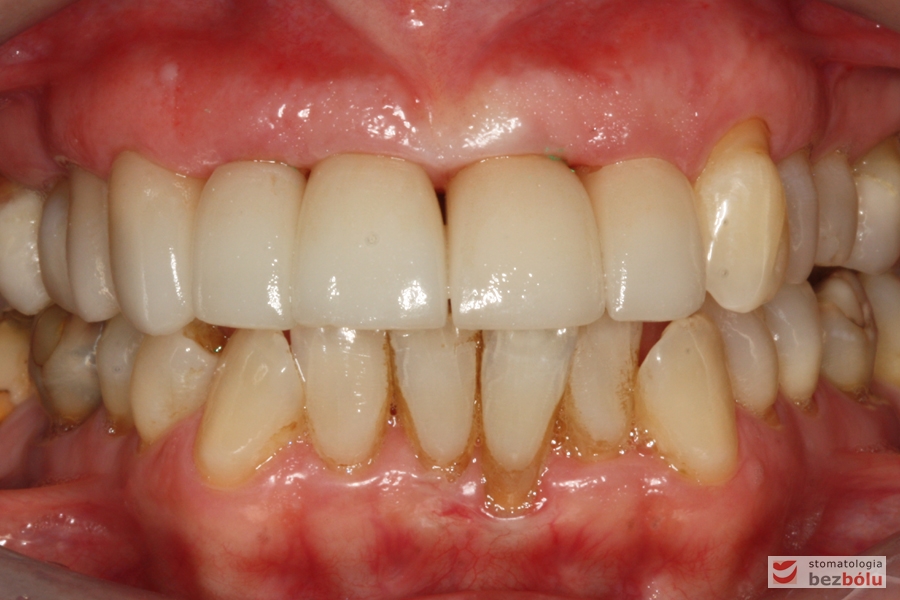

Efekt końcowy leczenia - nowe zęby w uśmiechu

Efekt końcowy leczenia – nowe zęby w uśmiechu